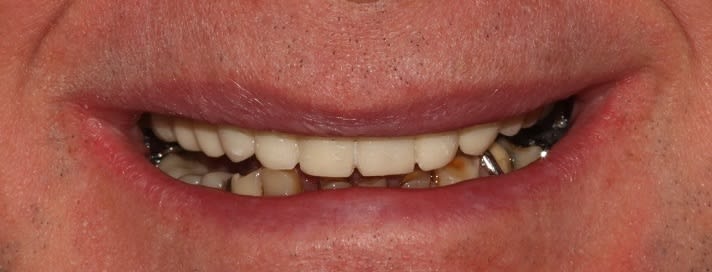

pour vous faire tchatcher un peu.

Cas simple, je n'ai pas les abdos pour assumer devant vous mes cas complexes, quand Enlaye et Pxav seront à la retraite on en reparlera.

Je fais mon autocritique avant vous, les cadrages sont dégueulasses et j'aurai pu nettoyer mieux mon ciment pro.

Le provisoire du haut à été réalisé ce matin en bloc technique, un peu plus de 3 h.

Le bas sera réalisé vendredi.

Enjoy!

Et putain, une photo en occ serrée, là on voit rien bougre d'âne!

(Au deuxième tour, je relèverai un peu la courbe de Spee sect 1. Au départ je pensais également rentrer un peu 24 25, mais en fait je pense que ça devrait s'équilibrer avec le bas, je vois en fin de semaine. Et le milieu est un peu décentré, mais au bout de 3h j'en avais marre)